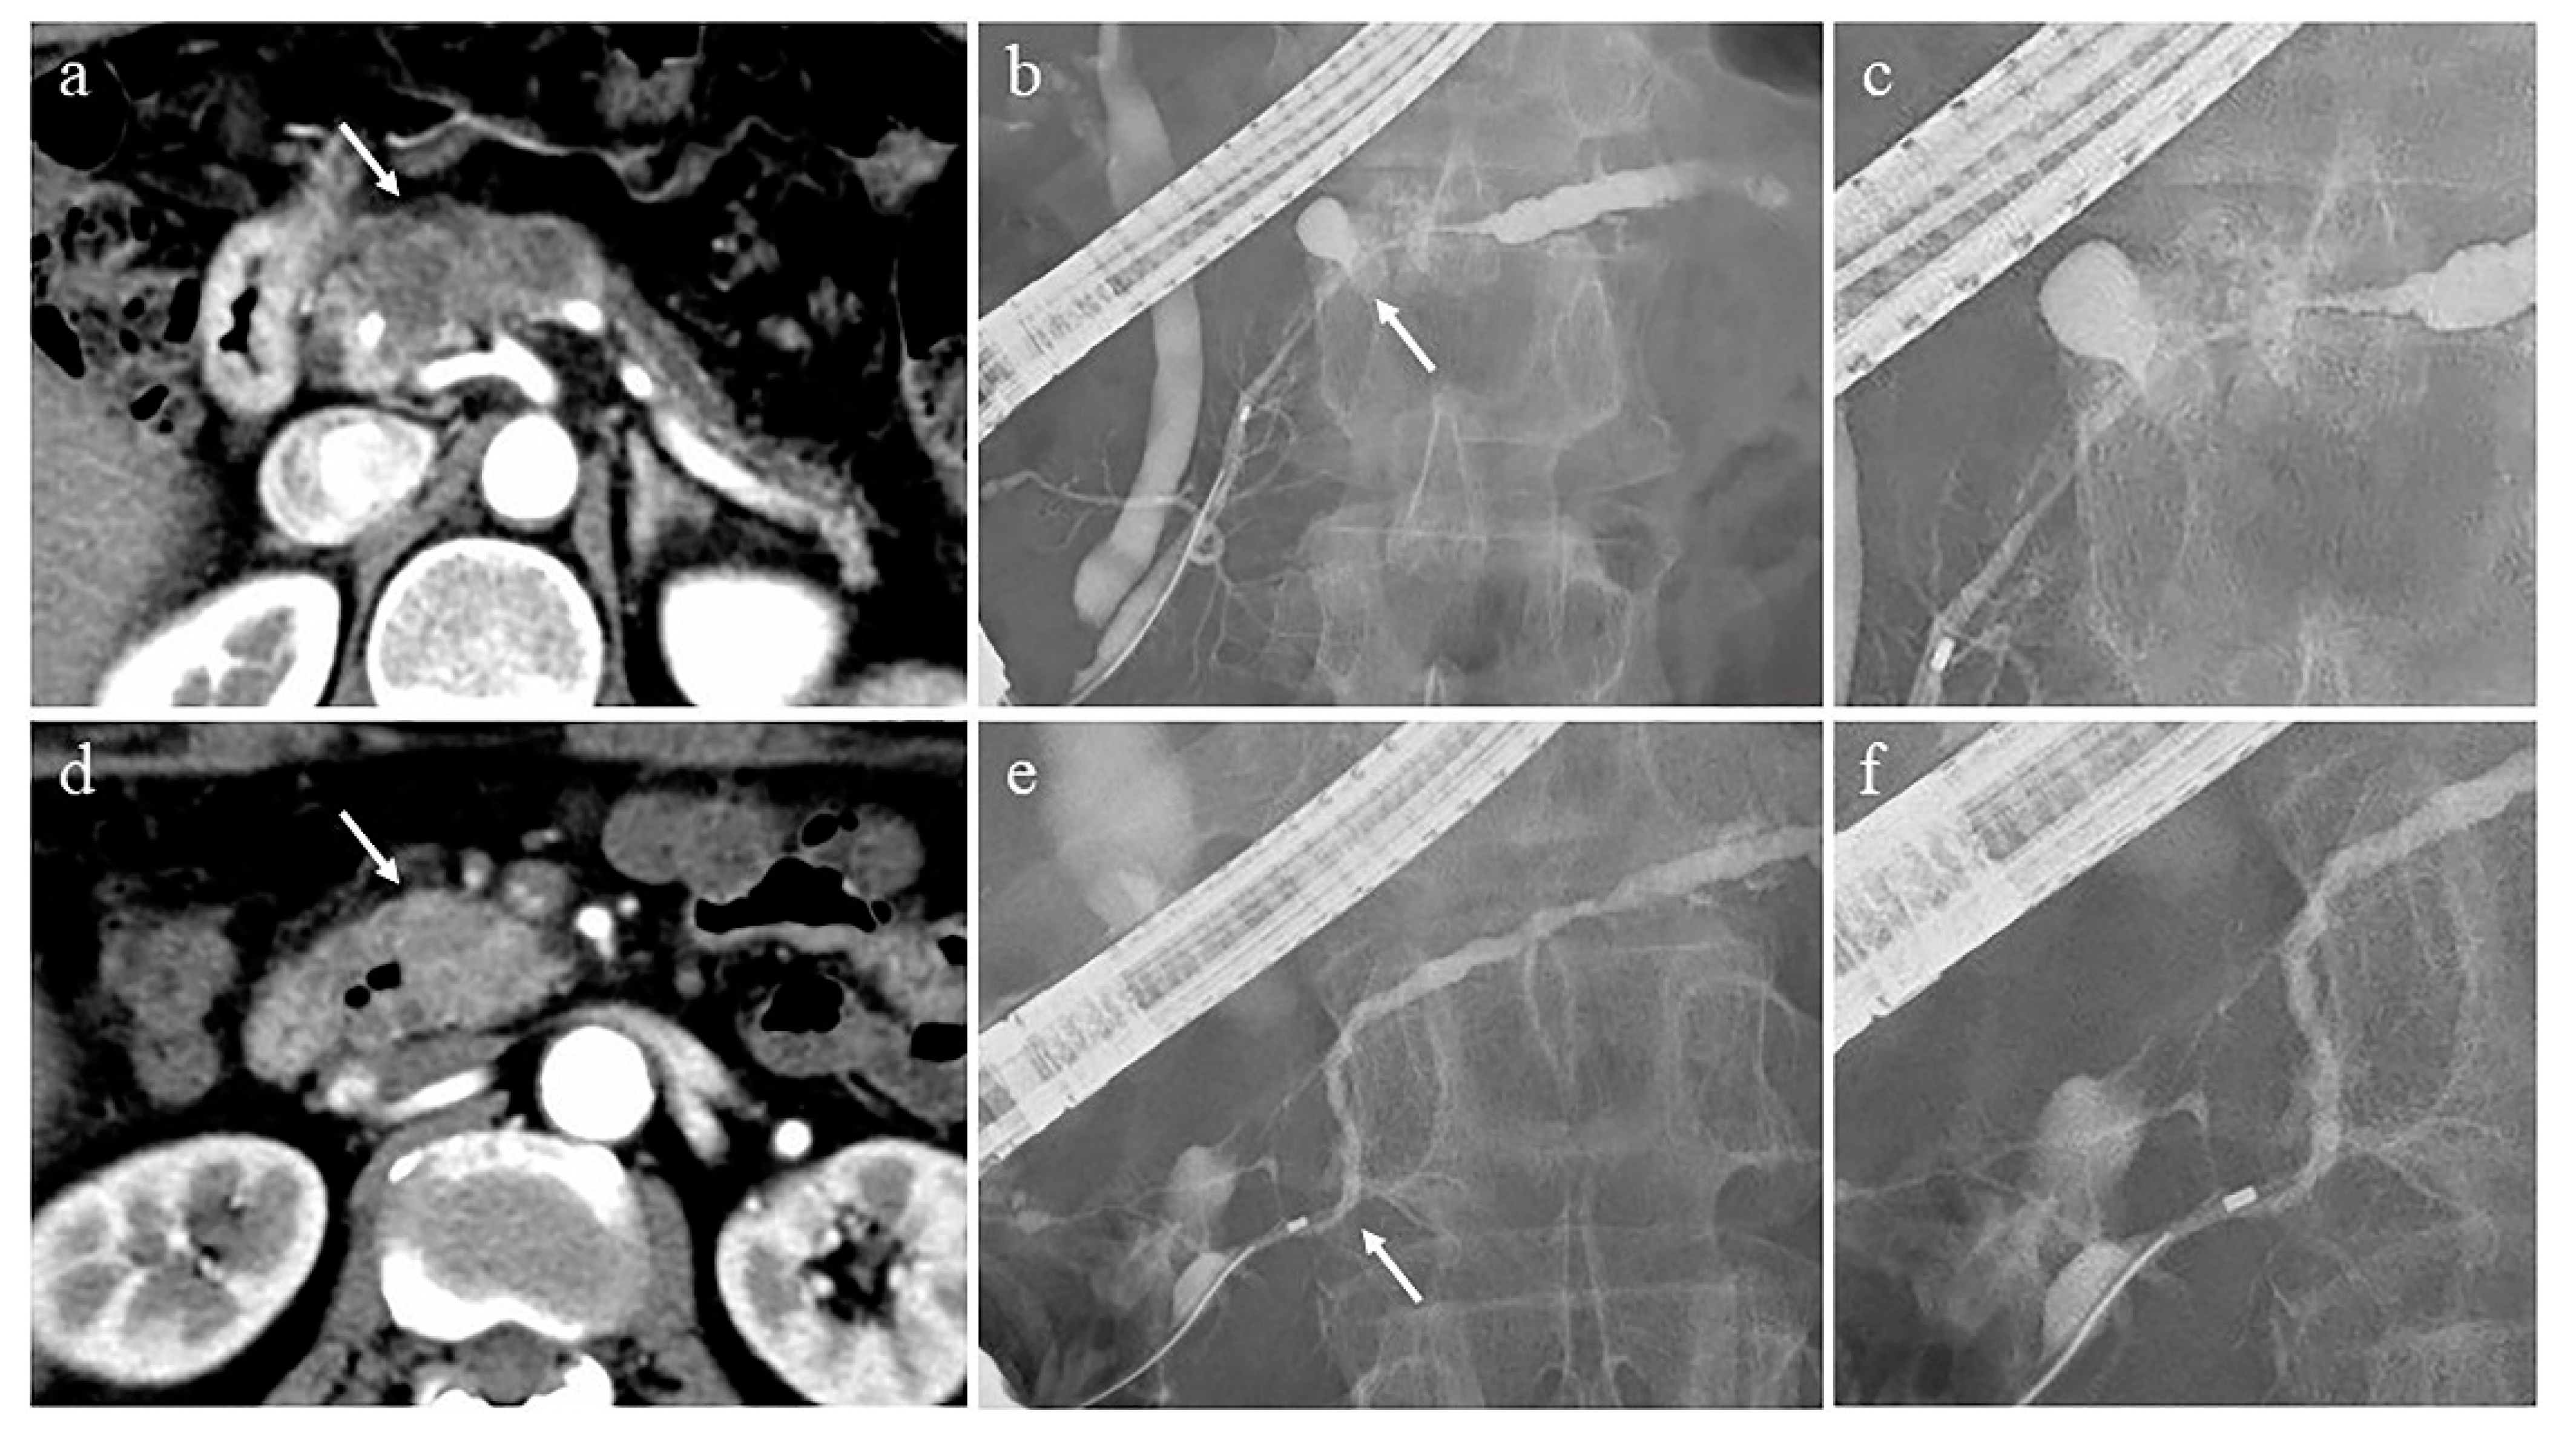

Evaluation of pancreatic duct images by ERP is important for the diagnosis of autoimmune pancreatitis (AIP) [93,94]. Diagnosis of AIP patients with diffuse pancreatic enlargement with a capsule-like rim [95] on CT or MRI is relatively easy and does not necessarily require ERP. On the other hand, AIP patients with atypical pancreatic parenchymal findings, such as focal pancreatic enlargement and mass formation, are difficult to distinguish from pancreatic cancer, and evaluation of the pancreatic duct image by ERP is important. The important ERP findings in the diagnosis of AIP are as follows [96]: long (> one-third the length of the pancreatic duct) stricture, lack of upstream dilatation from the stricture (<5 mm), multiple strictures, and side branches arising from the stricture site. In addition, it has been reported that the length of the narrowed portion of the main pancreatic duct (MPD) ≥ 3 cm, the side branches arising in the narrowed portion of the MPD, and the lack of upstream MPD dilatation from the narrowed portion were significantly more frequent findings in AIP than in pancreatic cancer, and useful for the differential diagnosis of AIP and pancreatic cancer [97,98] (Figure 2). MRCP is a simple and non-invasive imaging modality that is used to evaluate the pancreatic duct image of AIP. Its resolution is inferior to that of ERP [99], but it has the advantage of visualizing the upstream MPD when it is obstructed. MRCP images have been improved by advancements in MRI scanners and techniques, such as partial maximum intensity projection [100] and breath-hold compressed sensing accelerated three-dimensional MRCP [101]; MRCP findings have been added to the Japanese Clinical Criteria for Autoimmune Pancreatitis 2018 [94]. However, it is not possible to evaluate the derivation of the side branches arising from the narrowed portion of the MPD by MRCP, which is useful for the differential diagnosis of AIP and mass-forming pancreatitis from pancreatic cancer.

Figure 2.

Cases of pancreatic cancer (a–c) and autoimmune pancreatitis (d–f). (a) Computed tomography (CT) shows an irregular and hypovascular 3 cm-seized mass in the pancreatic body (arrow) and dilatation of the upstream main pancreatic duct (MPD). (b) Endoscopic retrograde pancreatography (ERP) shows the MPD stricture in the pancreatic body (arrow) and upstream MPD dilatation. (c) Deviation of side branches from the stricture site is not observed. (d) CT shows a 2 cm-sized mass with hypovascularity in the arterial phase in the pancreatic head (arrow). (e) ERP shows mild strictures of the Wirsung and Santorini ducts (arrow), and slight upstream MPD dilatation. (f) Deviation of side branches from the stricture site is observed.